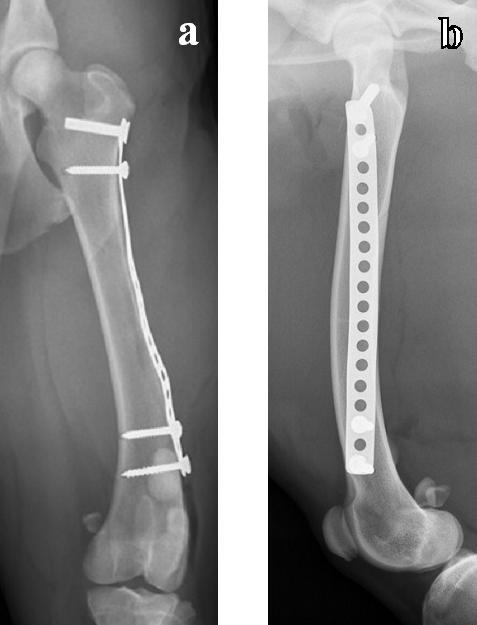

Validarea poziționării corecte a plăcii în raport cu osul și a selecției adecvate a dimensiunii și numărului șuruburilor s-a efectuat prin examenul imagistic radiografic convențional, utilizând incidențele clasice, medio-laterală și cranio-caudală (figura 21).

Investigațiile imagistice postintervenție au relevat integritatea articulația genunchiului și a articulației jaretului. Cartilajele articulare, epifizele și metafizele nu au suferit modificări. Amplasarea șuruburilor nu a modificat poziția fibulei, în raport cu tibia.

Figura 21. Imaginea radiografică a gambei după fixarea plăcii – incidență medio-laterală (a) și cranio-caudală (b)